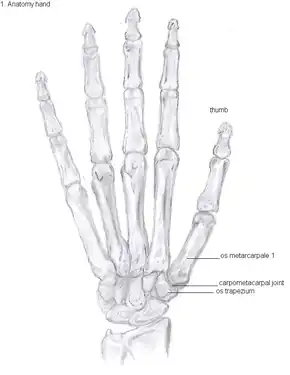

Bones of the hand

The TMC joint is a synovial joint between the trapezium bone of the wrist and the metacarpal bone at the base of the thumb. This joint is a so-called saddle joint (articulatio sellaris), unlike the CMC joints of the other four fingers which are ellipsoid joints.[13] This means that the surfaces of the TMC joint are both concave and convex.

This shape provides the TMC joint a wide range of motion. Movements include:[14]